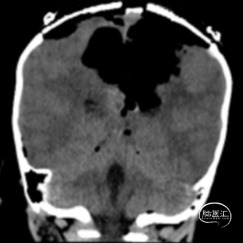

双侧额顶叶中线旁脑实质内团片状异常信号影,呈明显花环状强化,累积脑膜及胼胝体压部,性质待定,恶性胶质瘤?

非典型畸胎瘤样/横纹肌样瘤( AT /RT) 是发生在儿童中枢神经系统的少见的具有极大侵袭性的恶性肿瘤,在儿童中枢神经系统肿瘤中发病率极低。CT平扫多表现为混杂密度,也可等或稍高密度,呈不均匀或均匀强化,瘤内常可见囊性变及瘤周低密度水肿带。MRI扫描T1加权像为低信号,T2加权像为等信号或高信号,肿瘤实质与灰质信号相似或稍高,增强扫描可见中等至明显 增强,等信号时可能与肿瘤细胞密集,细胞核比例大而含水量相对较少有关。AT /RT是原发于中枢神经系统、好发于儿童、极其少见、侵袭性极高的胚胎性肿瘤,临床表 现及影像学无特异性,确诊有赖于组织病理。最大限度的安全切除,并辅以放化疗,可改善患者预后,但总体预后仍然很差。